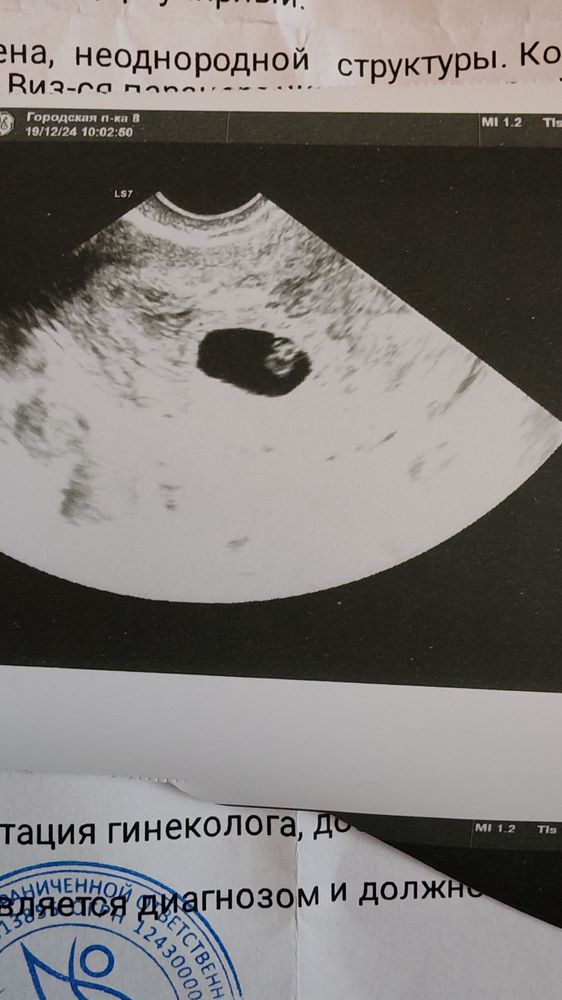

Наденька, отслеживала и овуляцию и тесты были положительные на 10дпо на 19дпо первое узи там еле разглядела пя но было 2-3мм , потом на 26 день , 26 ноября второе узи пя 7мм но эмбриона еще не было , был желточный мешок. И вот 19 декабря.. Эмбрион 6мм по узи в жк и ставят 6нелель , в платной в этот же день вообще сказали 4мм.. 🙄 и там де вот взяли хгч , сейчас пришел анализ, просто если 6 недель это типо оплодотворение попадает на ноября, а у меня уже узи было с пя в 2-3мм от 19 числа и положительные тесты с 10числа . и сердцебиение не сказали , мерцание есть, сердцебиение нет , типо рано... Но как рано если 9нелель должно быть, даже ладно пусть погрешностью будет неделя и 8.. Все равно уже должно быть. Тут читала что плод бывает медленно замирает и вместо сердцебиения как раз мерцание .

Алена, да я выжидаю дни и пойду на узи вот последний мне дали в жк снимок 19 декабря.. И 26 ноября предыдущий 26 не было видно эмбриона но она мне показывала желточный мешок был и сказала вот там будет эмбрион

Александра , вообще динамика для такой разницы во времени не очень… но все равно вы ничего толком не поймете пока не повторите узи.